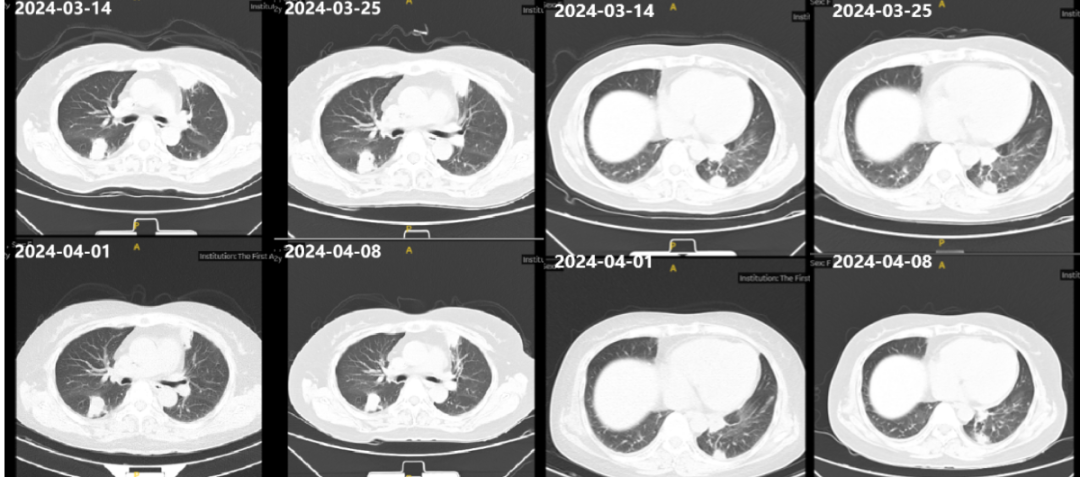

图3.抗真菌治疗过程中胸部CT影像

予